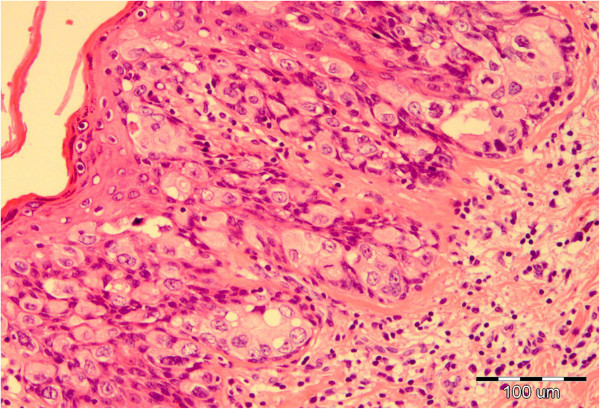

See Paget cells with abundant amphophilic, clear cytoplasm in image

What is suggested by the following:

Cells spitting out into corneum

Crushing of basal layer

Amphophilic cells

Paget’s disease